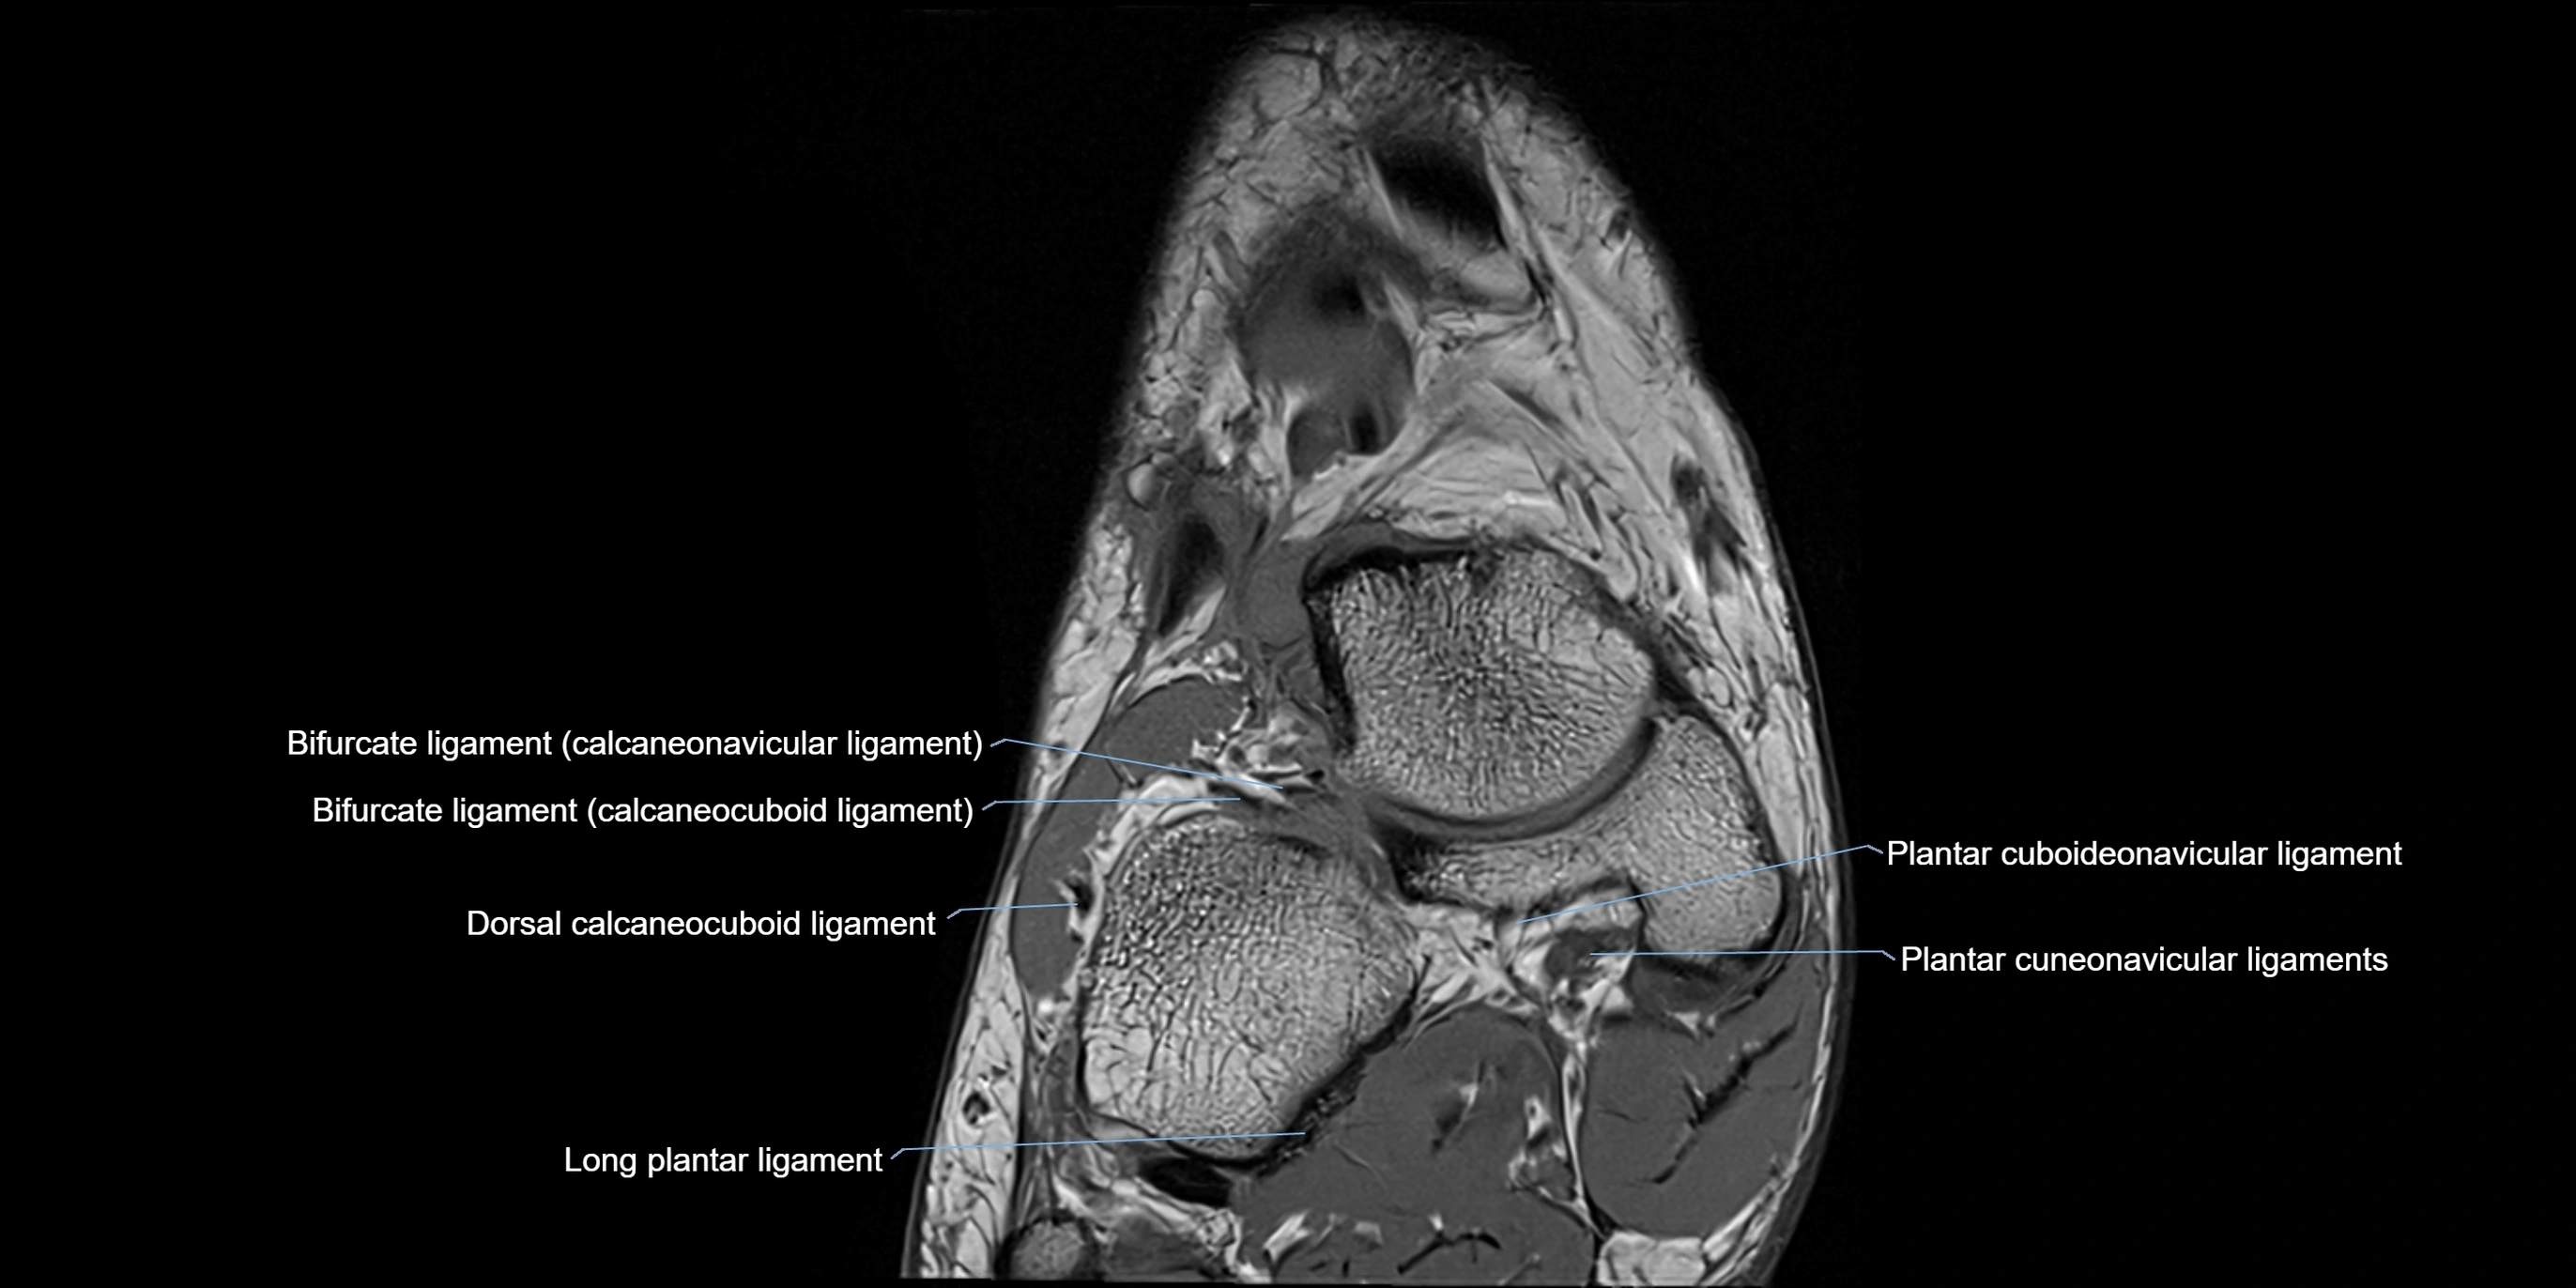

MRI image

image